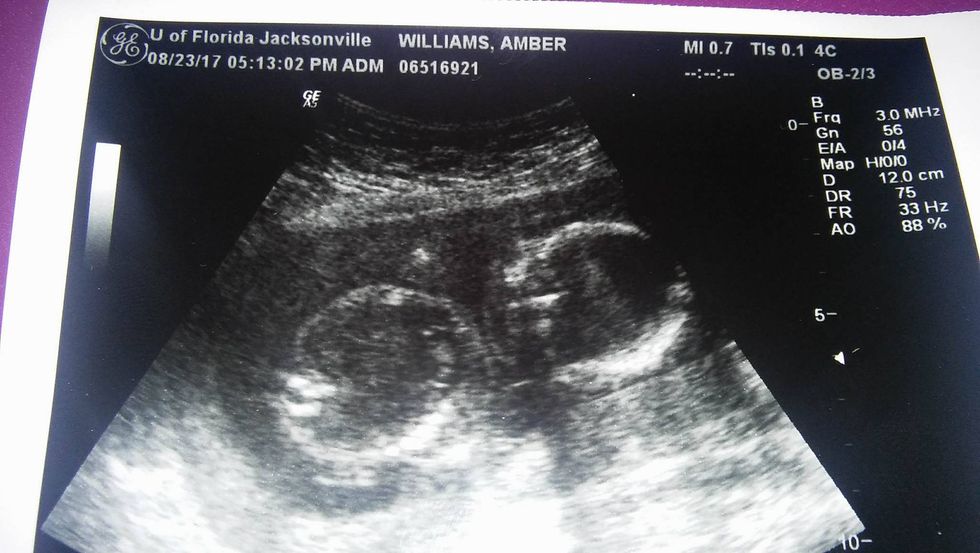

This was the first time I had seen my baby since I was 14 weeks, and the baby had gotten so much bigger. I was so happy to see my baby growing. Unfortunately, the midwife couldn't find a heartbeat, so she called in a doctor. She was also unable to find the heartbeat. I was 20 weeks along, but the baby was only measuring at 17 weeks. They apologized to me, and I began crying no matter how hard I tried not to. They left for a couple minutes, and then they came back.

Upon getting to the hospital, they knew exactly who I was by my name, and had my room ready. I asked for a ultrasound before anything, and the doctor agreed. The last thing I wanted to do was induce, and kill my baby if they were wrong. They did the ultrasound, only to show no change from the day before: no heartbeat. I felt my heart breaking over, and over again. All I wanted to do was scream, but all I did was cry. I began the process of inducing that afternoon, and had my baby the next morning. It was a boy, and he was so small that my heart broke all over again. It was about 2 hours before I even held him, after giving birth to him.